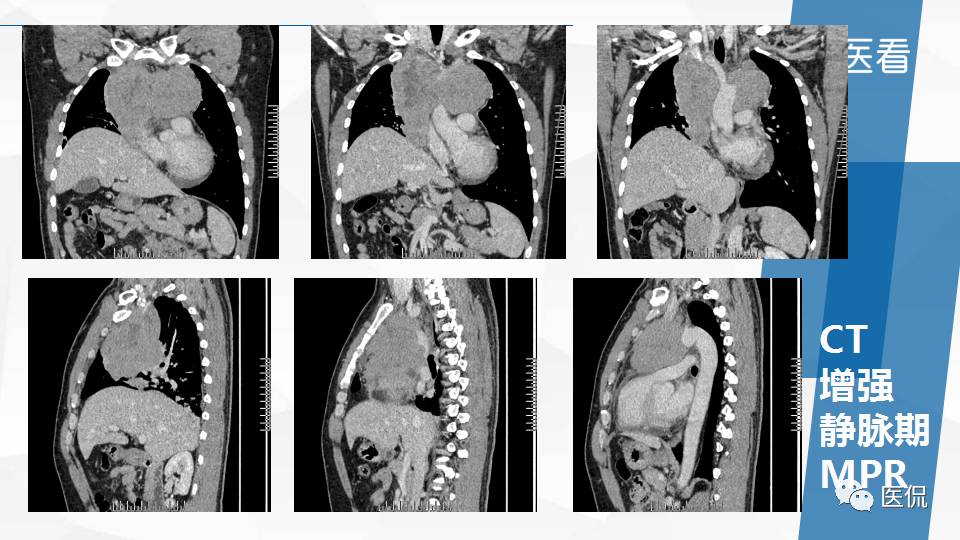

纵隔精原细胞瘤案例 (精原细胞瘤影像表现与鉴别诊断)

精原细胞瘤ct影像,精原细胞瘤影像特征